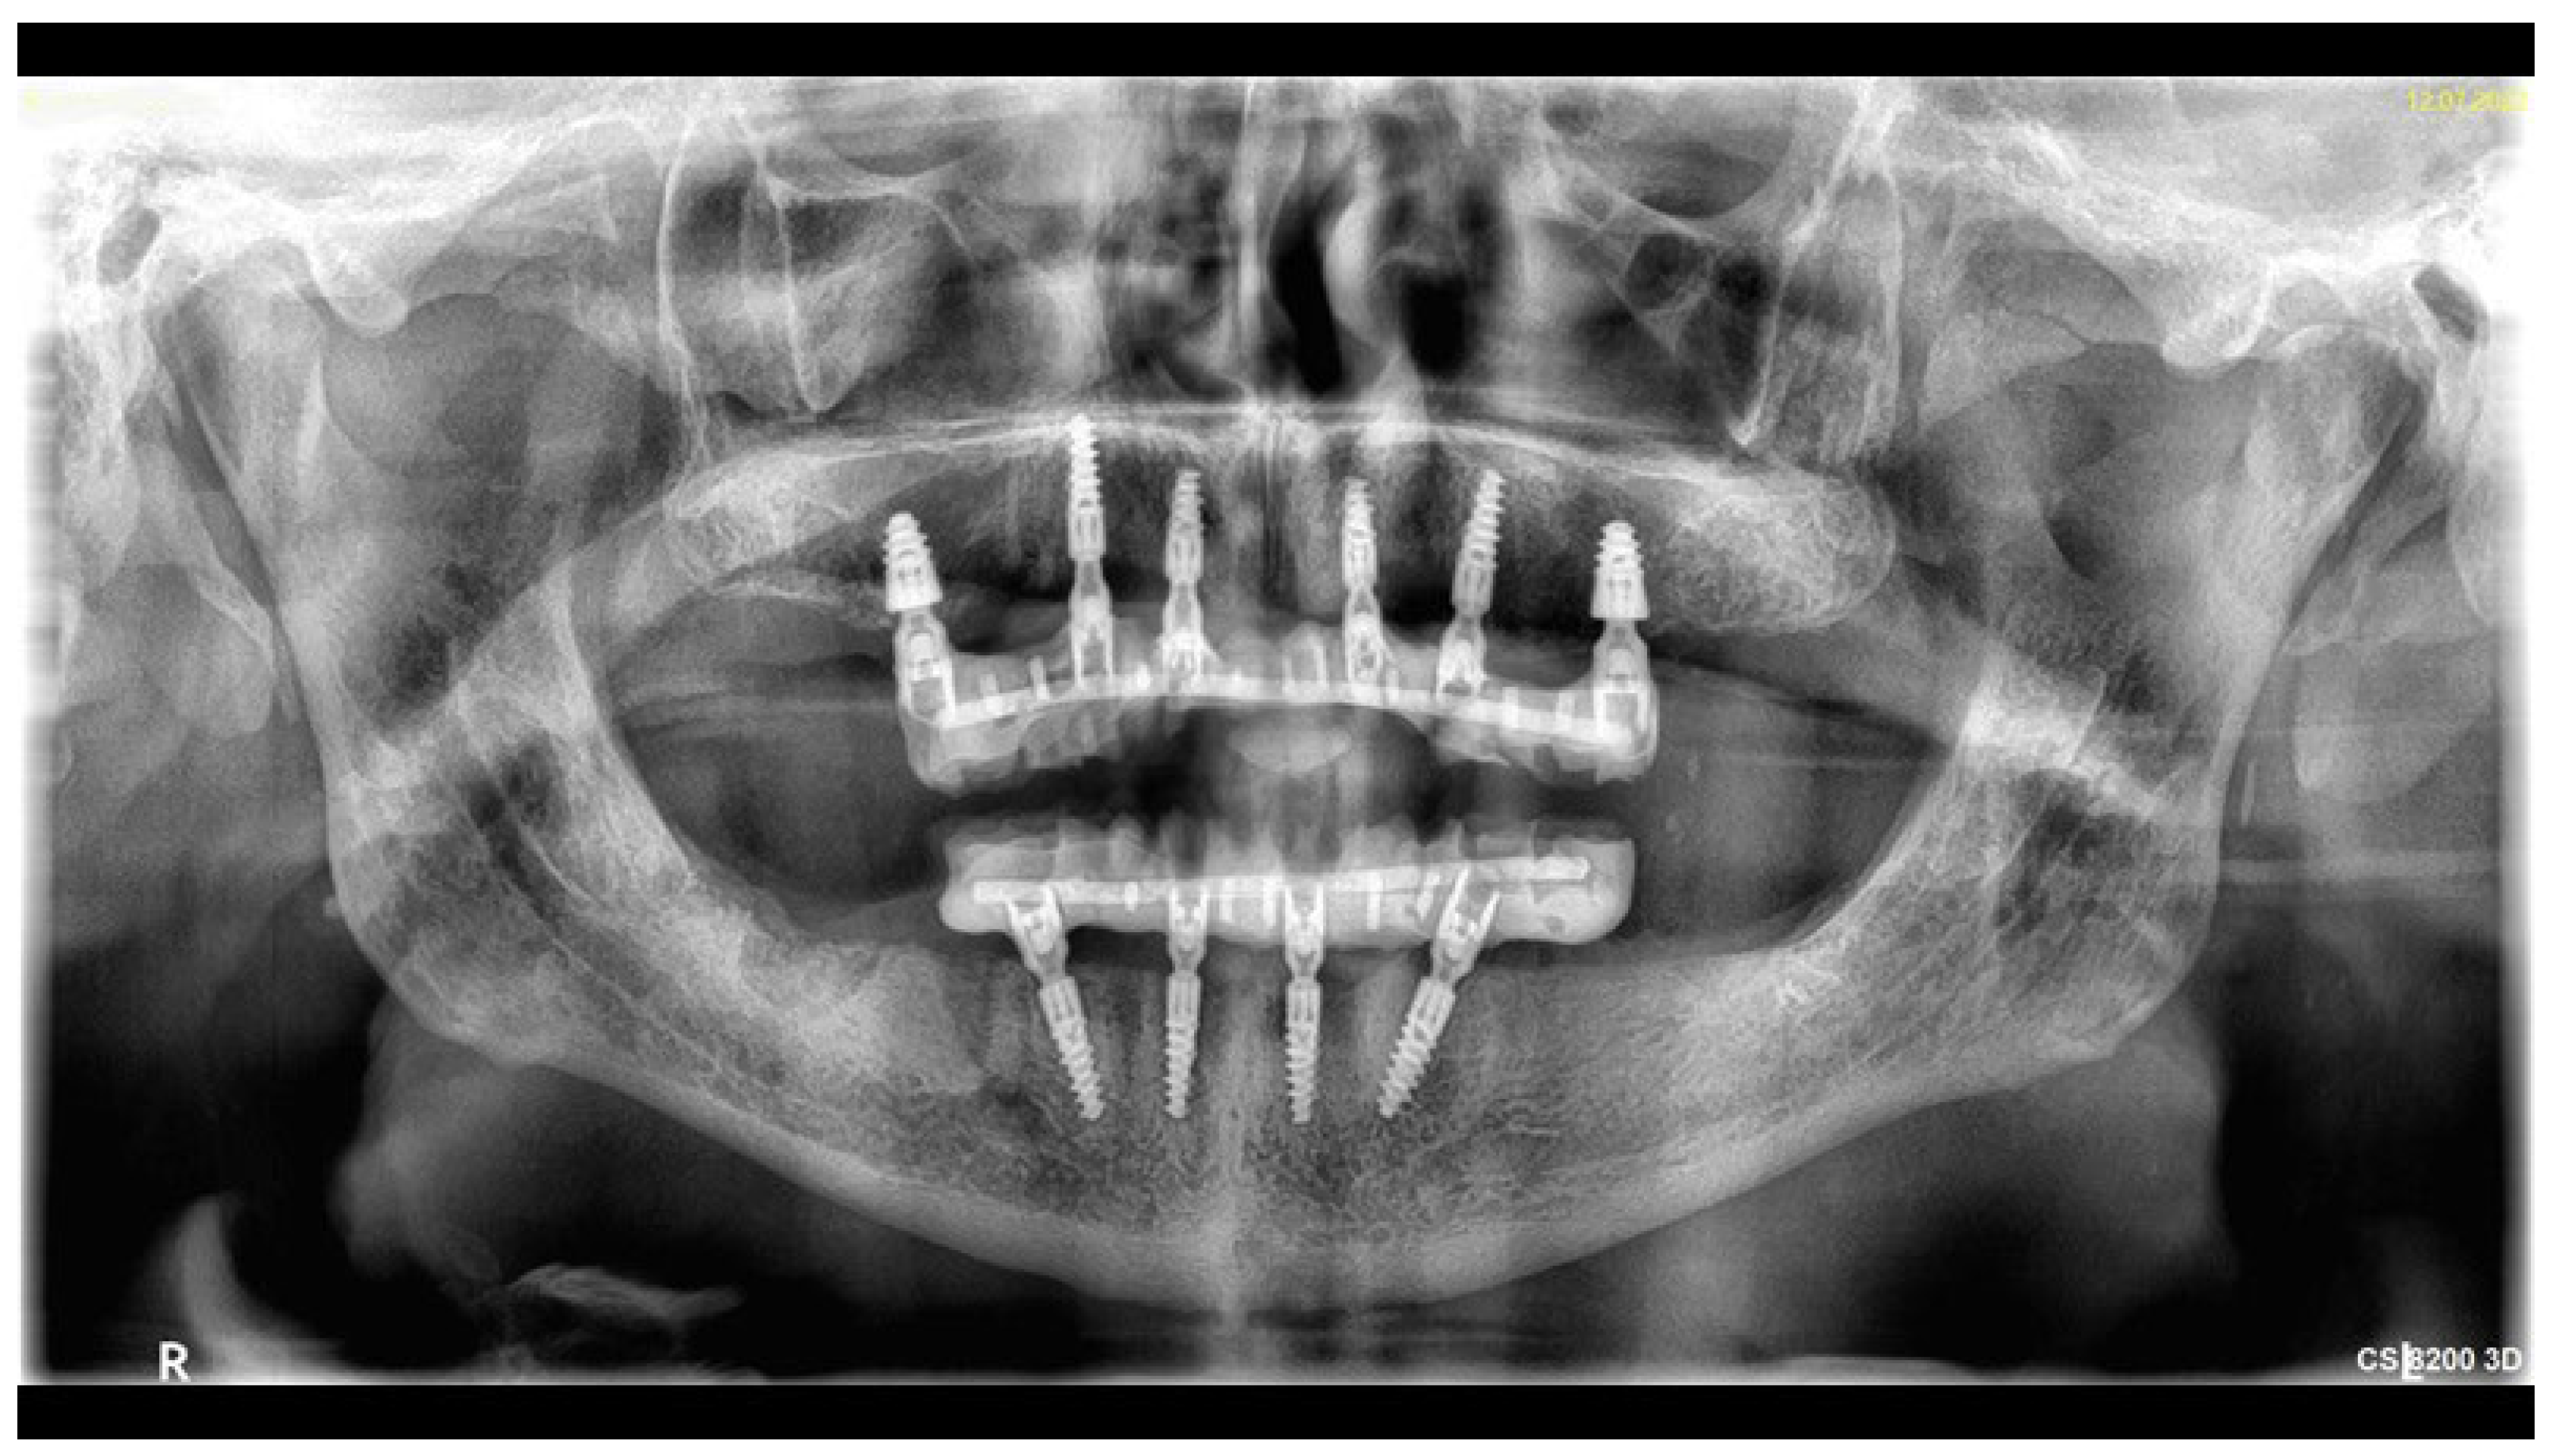

- One-day surgery with implant placement, MUA, and intraoral welding to obtain immediately loaded long-lasting temporaries.

- The conduction of an analogue impression, an I.O. scan, a removable 360° scan, and a scanflag scan.

- The conduction of a Sheffield passive fit test of 3D-printed try-ins on a milled titanium bar.